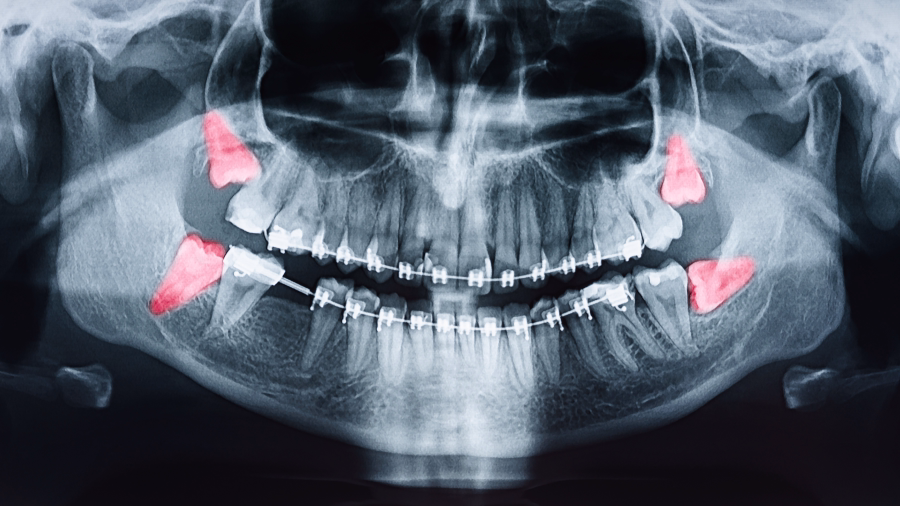

Consultation and Digital Imaging

We use 3D CT scans to assess the exact position and root structure of your wisdom teeth, so there are no surprises.